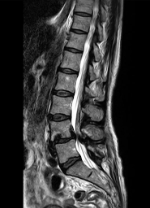

Imagen en alta resolución. Este enlace se abrirá mediante lightbox, puede haber un cambio de contextoLa estenosis de canal lumbar es la disminución de los diámetros del canal lumbar en donde se encuentran la parte final de la médula espinal y por el que transcurren los nervios, a través de la columna vertebral, responsables del movimiento en los miembros inferiores y del control de esfínteres. Este estrechamiento provoca que, cuando la columna se mueve, las raíces son comprimidas produciendo una dificultad en su irrigación y en su funcionamiento. Como consecuencia, la persona que sufre esta enfermedad presenta dolor lumbar en las piernas y los trastornos sensitivos en forma de hormigueo y sensación de pérdida de fuerza al caminar apenas 100 metros, lo que le obliga a detenerse.

Por ello, se denomina síndrome del escaparate, ya que el paciente se tiene que parar unos minutos para que desaparezcan los síntomas.